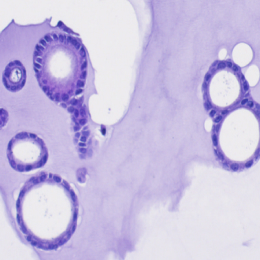

H&E | ANXA1 | ANXA10 | ANXA13 | |

|---|---|---|---|---|

Cancer tissue | ![]() | ![]() | ![]() | ![]() |

Cancer organoid | ![]() | ![]() | ![]() | ![]() |

Unlock the essence of precision in cancer treatment with our PC organoids, mirroring the genetic markers of pancreatic cancer.

Experience the future of testing your drugs, serving as an invaluable tool in capturing the patient-specific characteristics, thereby providing a more accurate platform for studying tumor biology and testing.